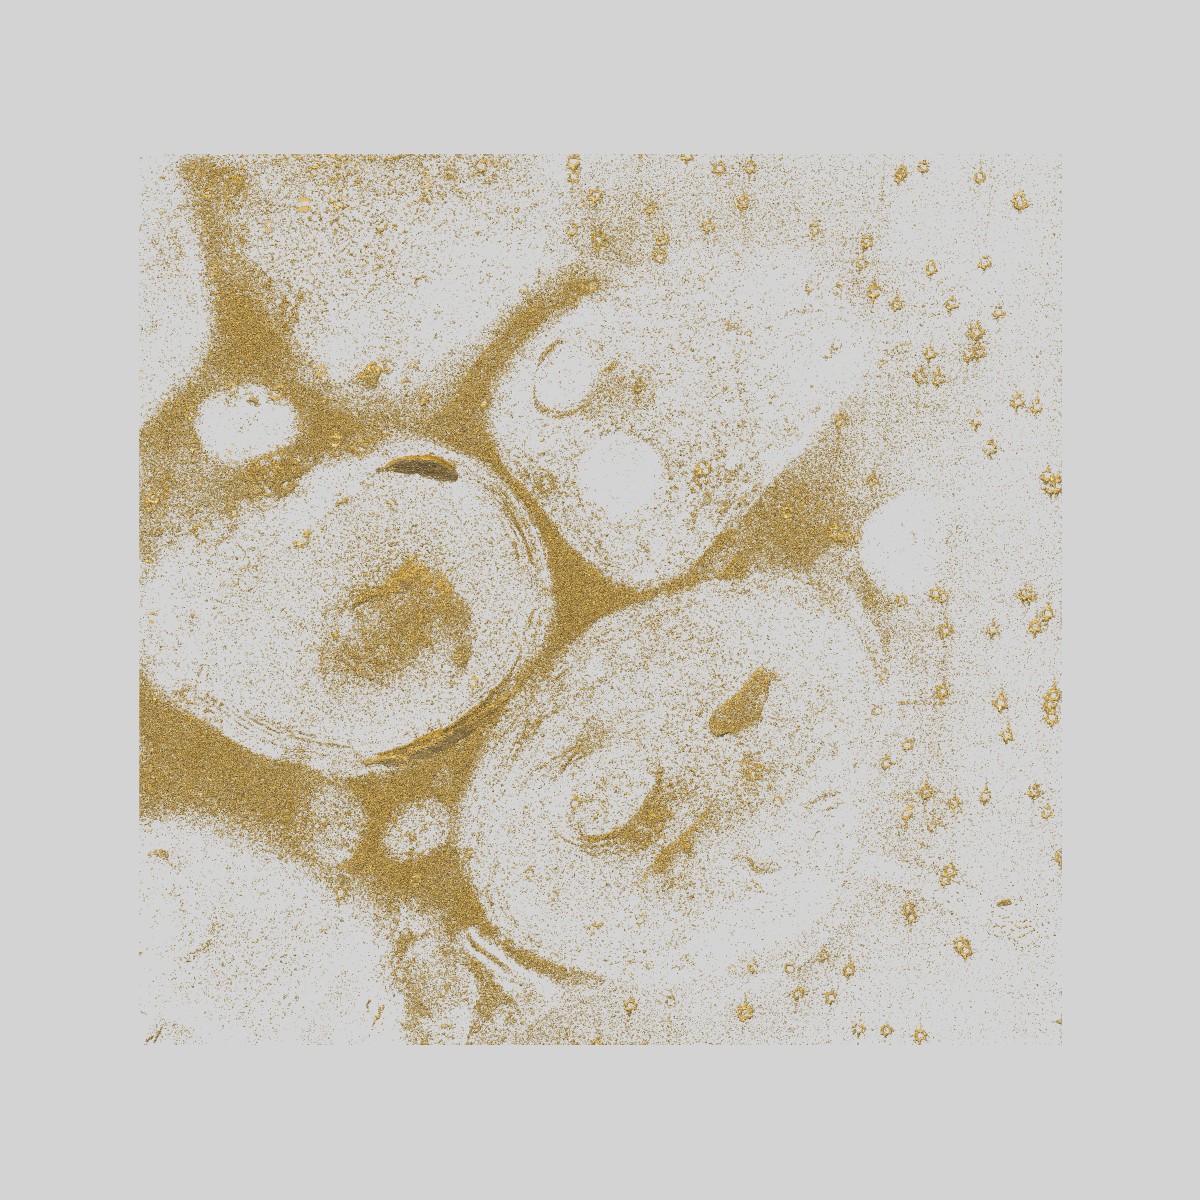

Malaria infected red blood cell section showing a schizont at an intermediate stage in parasite egress

Sample Organism: Plasmodium falciparum 3D7

Sample: Plasmodium falciparum infected human erythrocyte treated with the egress inhibitor E64

Parasitophorous vacuole poration precedes its rupture and rapid host erythrocyte cytoskeleton collapse in Plasmodium falciparum egress.

Hale VL , Watermeyer JM, Hackett F, Vizcay-Barrena G, van Ooij C, Thomas JA , Spink MC, Harkiolaki M, Duke E, Fleck RA , Blackman MJ, Saibil HR

(2017) PNAS , 114 , 3439 - 3444